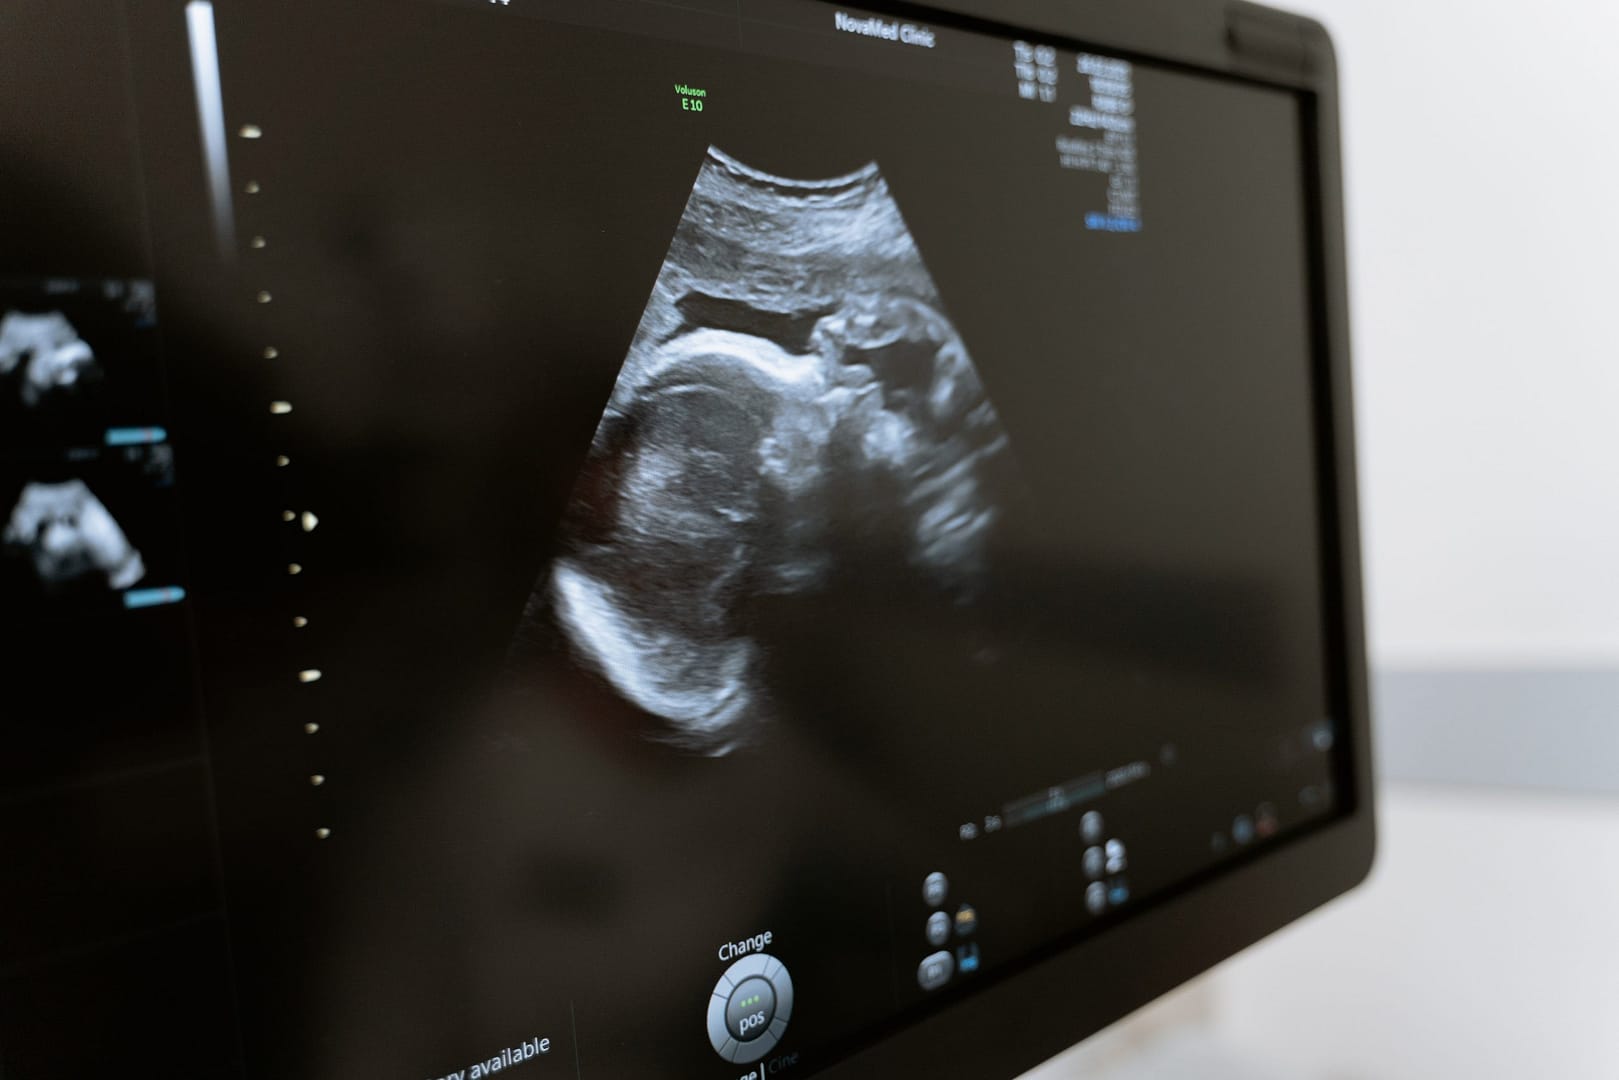

என் குழந்தை எப்படி இருக்கும்?

உங்கள் குழந்தை அல்லது கரு, தலையில் இருந்து கால் வரை சுமார் 11.6cm நீளம் கொண்டது. எடை சுமார் 100 கிராம்.

உங்கள் குழந்தை இப்போது முகத்தை இழுக்கத் தொடங்குகிறது, எந்த ஒரு புன்னகையும் அல்லது முகச்சுருக்கமும் முற்றிலும் சீரற்றதாக இருக்கும், ஏனெனில் இதுவரை தசைக் கட்டுப்பாடு இல்லை.

நரம்பு மண்டலம் தொடர்ந்து வளர்ச்சியடைகிறது, மேலும் இது உங்கள் குழந்தை தனது கைகளையும் கால்களையும் அசைக்க ஆரம்பிக்க உதவுகிறது. உங்கள் குழந்தையின் கைகள் முஷ்டிகளை உருவாக்கலாம், மேலும் அவை உங்களுக்குள்ளும் குத்த ஆரம்பிக்கலாம்.